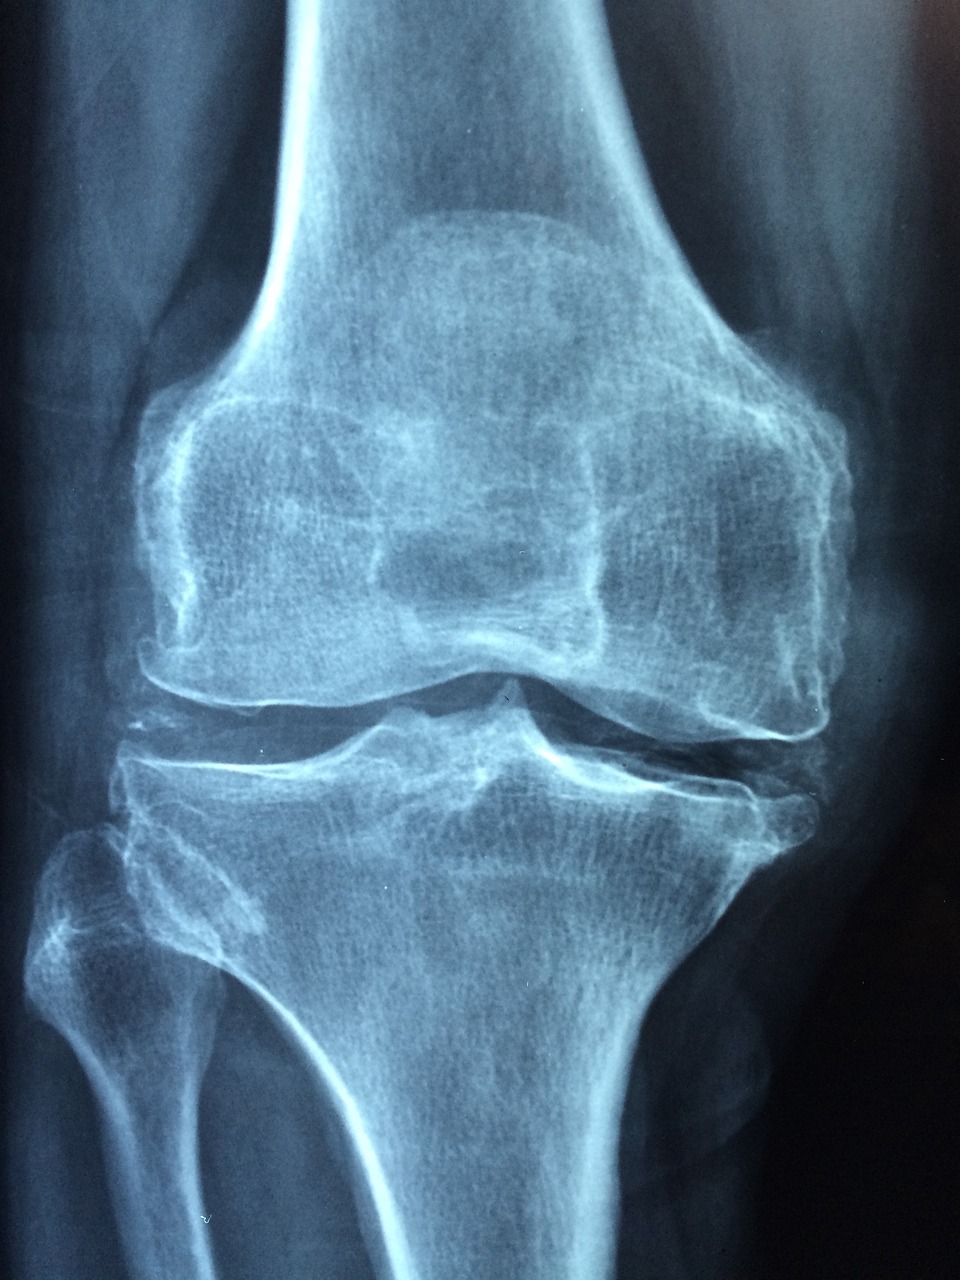

골다공증은 뼈의 밀도와 강도가 약해져 쉽게 골절되는 질환으로, 특히 중장년층과 고령자에게서 자주 발생합니다. 초기에는 뚜렷한 증상이 없어 조기 발견이 어렵지만, 예방과 관리만 잘해도 충분히 진행을 막을 수 있습니다. 이 글에서는 골다공증의 주요 원인인 호르몬 변화, 잘못된 식습관, 그리고 유전적 요인을 중심으로 그 원인들을 깊이 있게 분석해 보겠습니다.

골다공증은 유전적인 영향도 큽니다. 부모나 형제자매 중 골다공증을 앓은 사람이 있다면, 자신도 고위험군에 속할 가능성이 높습니다. 이는 뼈의 크기, 밀도, 대사 속도 등 유전적으로 결정되는 요소가 많기 때문입니다. 특히 체형이 작고 마른 여성, 유년기나 청소년기에 충분한 칼슘 섭취나 운동을 하지 못한 경우, 유전적 요인과 환경적 요인이 복합적으로 작용하여 골다공증 위험이 더욱 커집니다. 또 폐경 시기가 빠를수록 골다공증에 취약해지는 경향이 있으며, 이러한 경향은 가족력과도 연관될 수 있습니다. 유전적 요인이 있다고 해서 반드시 골다공증에 걸리는 것은 아니지만, 이 경우 더욱 철저한 예방이 필요합니다. 골밀도 검사 주기를 짧게 가져가고, 조기 진단 및 치료를 통해 진행을 늦추는 것이 핵심입니다. 가족 중 골다공증 병력이 있다면 의료진과 상담을 통해 개인 맞춤형 예방 전략을 세우는 것이 좋습니다. 골다공증은 단순히 뼈가 약해지는 질병이 아니라, 호르몬 변화, 영양 결핍, 유전 등 다양한 원인이 복합적으로 작용하는 질환입니다. 특히 중년 이후에는 그 위험이 급격히 증가하므로, 조기 진단과 체계적인 예방이 무엇보다 중요합니다. 건강한 식습관과 규칙적인 운동, 정기적인 검진을 통해 누구나 뼈 건강을 지킬 수 있습니다. 오늘부터라도 실천 가능한 예방법을 시작해보세요.